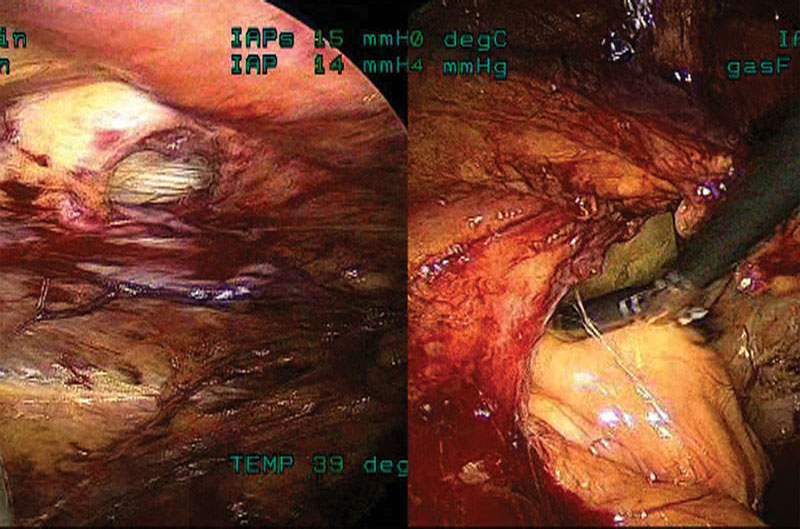

In the patient with a right groin inguinal hernia recurrence, the mesh (similar in type to the dual-layered heavyweight polypropylene shown in the previous video) has contracted about 90% from its original size. (Figure 1)

The patient in Video 4 had postoperative groin pain. The mesh can be seen contracted inferior to the tacks, which no longer penetrate the contracted mesh. (Figure 2)